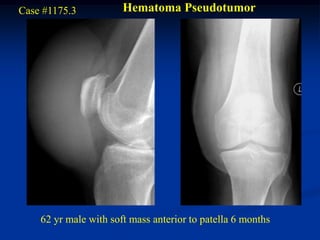

Case #1175.3           Hematoma Pseudotumor

62 yr male with soft mass anterior to patella 6 months